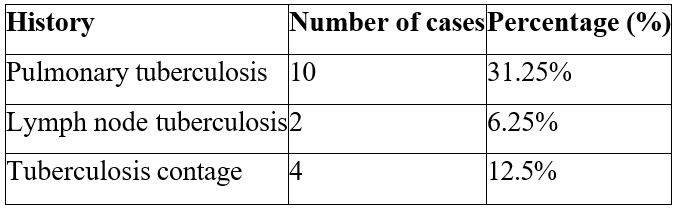

1/ Medical History: Extra-urinary tuberculosis was found in 12 patients (37.5% of all cases), pulmonary tuberculosis was associated with urogenital tuberculosis in 10 patients, and lymph node tuberculosis was found in 2 patients. The notion of family contact was identified in 4 patients (Table 1).

Table 1: Breakdown of patients' pathological histories.